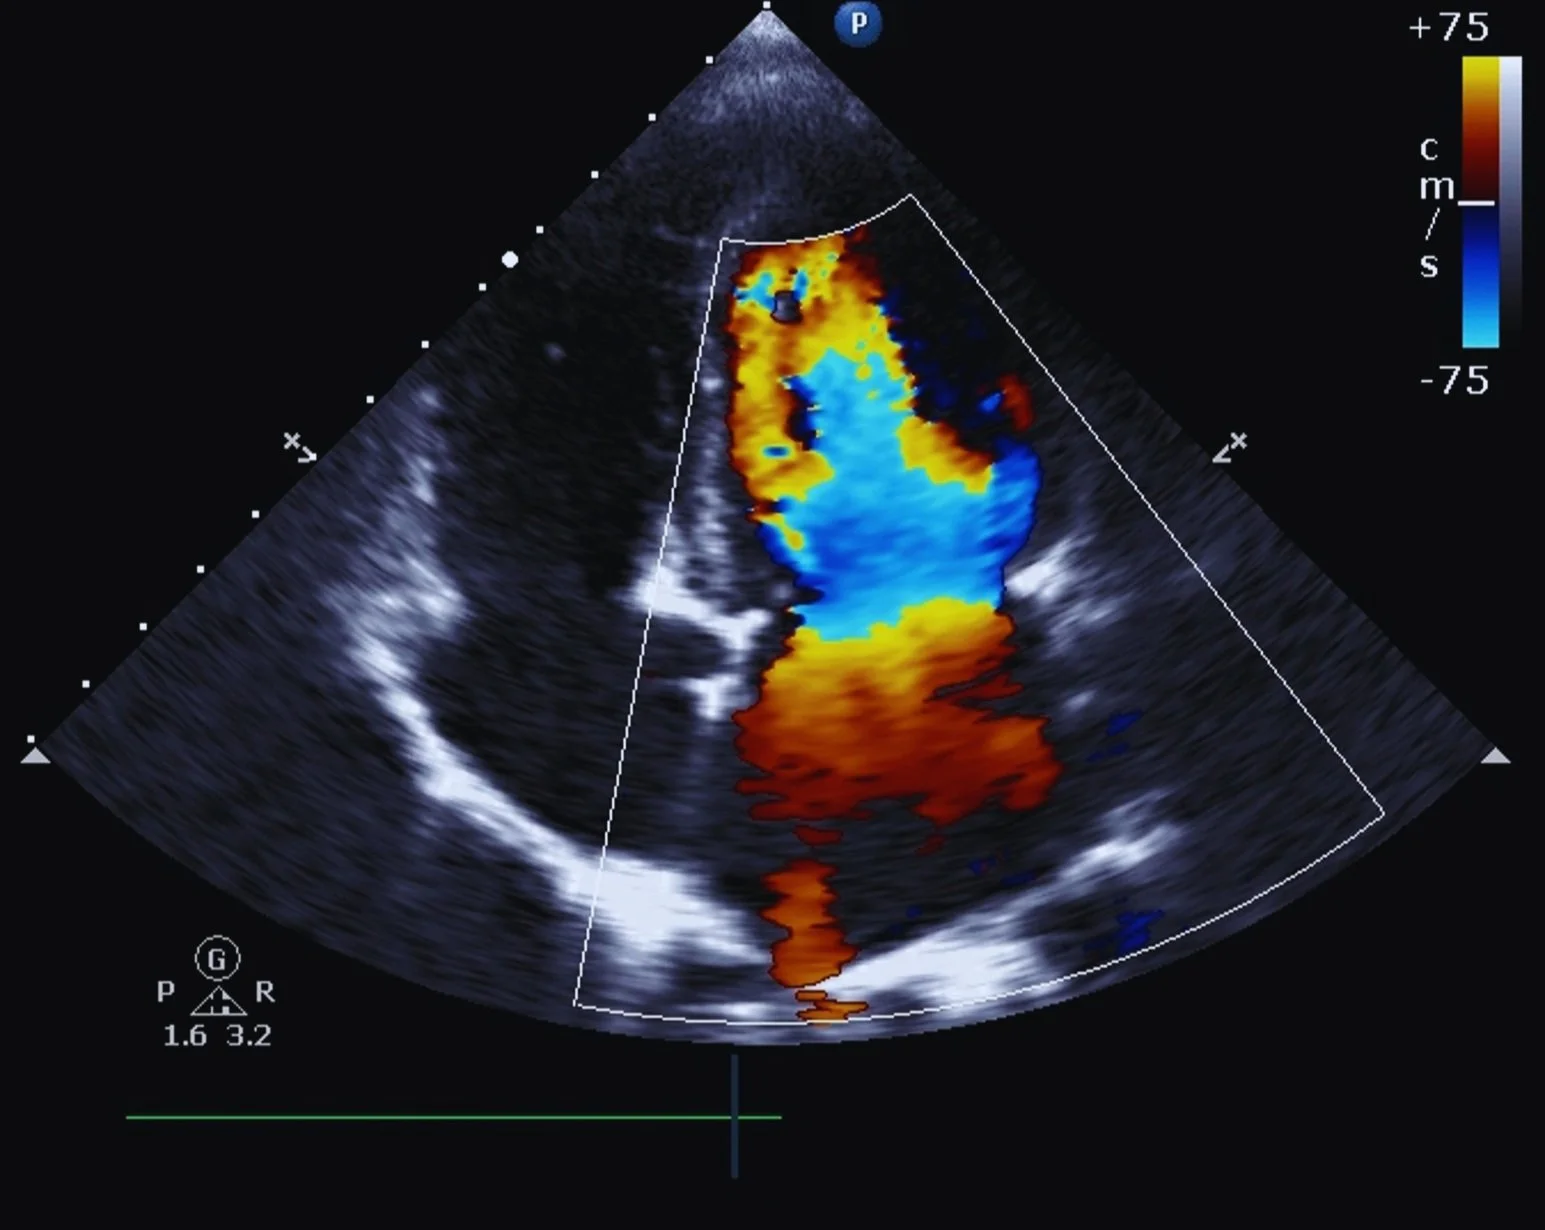

A stress echo is similar to a treadmill stress test, but it adds ultrasound imaging of your heart before and after exercise. This gives your doctor a detailed look at how well your heart muscle is pumping and whether certain areas are not getting enough blood during activity.

It’s especially useful for diagnosing coronary artery disease and evaluating how well the heart is functioning.